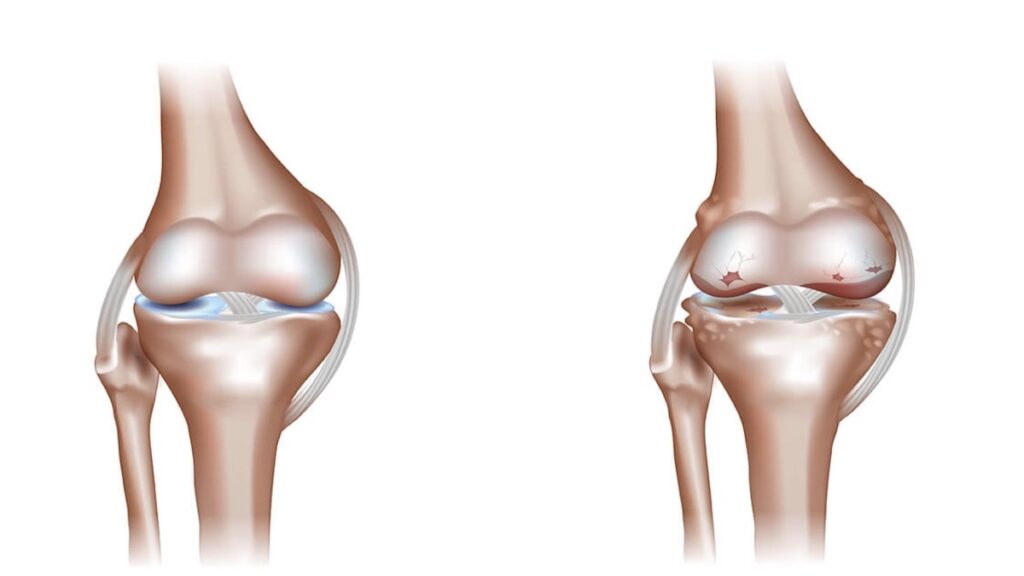

A bone graft is a surgical procedure used to repair fractures or tears in bones by fixing the damaged bone pieces using plates or surgical screws, usually in the form of a patch on the bone’s surface. Bone grafts help restore bone stability, promote healing, and are used in a variety of cases that require surgical bone fixation, including:

- Bone grafting is used to help stimulate the healing of bones in areas where natural healing is slow or challenging. It can create an optimal environment for fractured or weak bones to recover and heal.

- It can replace lost bone due to accidents, tumor removal, or bone diseases, helping restore the function and natural structure of bones.

- Bone grafting can enhance the stability of fractured or cracked bones by fixing bone fragments.

- This procedure is used to correct structural deformities or bone deviations, improving appearance and function.